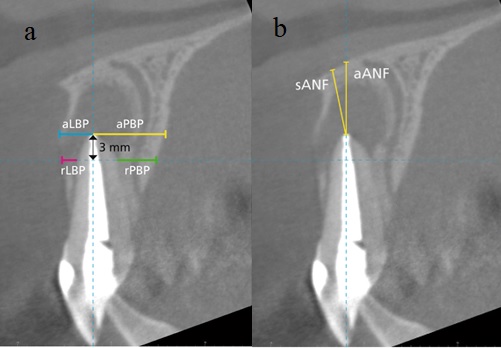

1. Distancia (mm) de la raíz a las tablas óseas vestibular y palatina en dos niveles diferentes medidos en el plano sagital (figura 1):

a. Distancia del ápice a las tablas óseas vestibular (ALBP) y palatina (APBP), medidas perpendicularmente al eje longitudinal del diente.

b. Distancia de la superficie radicular a las tablas óseas vestibular (RLBP) y palatina (RPBP) a 3 milímetros del ápice, medidas perpendicularmente al eje longitudinal del diente.

Notas: a) Distancia (mm) de la raíz a las tablas óseas vestibular y palatina en dos niveles diferentes; b) distancia (mm) del ápice al piso nasal en el plano sagital TCHC. Imagen tomada de Ducommun et al. (3).

2. Distancia (mm) del ápice al piso nasal medida en el plano sagital (figura 2):

a. Distancia más corta del ápice al piso nasal (SANF).

b. Distancia del ápice al piso nasal en la extensión del eje longitudinal del diente (AANF).

Notas: a) Diente con indicación de microcirugía apical; b) diente sin indicación de microcirugía apical